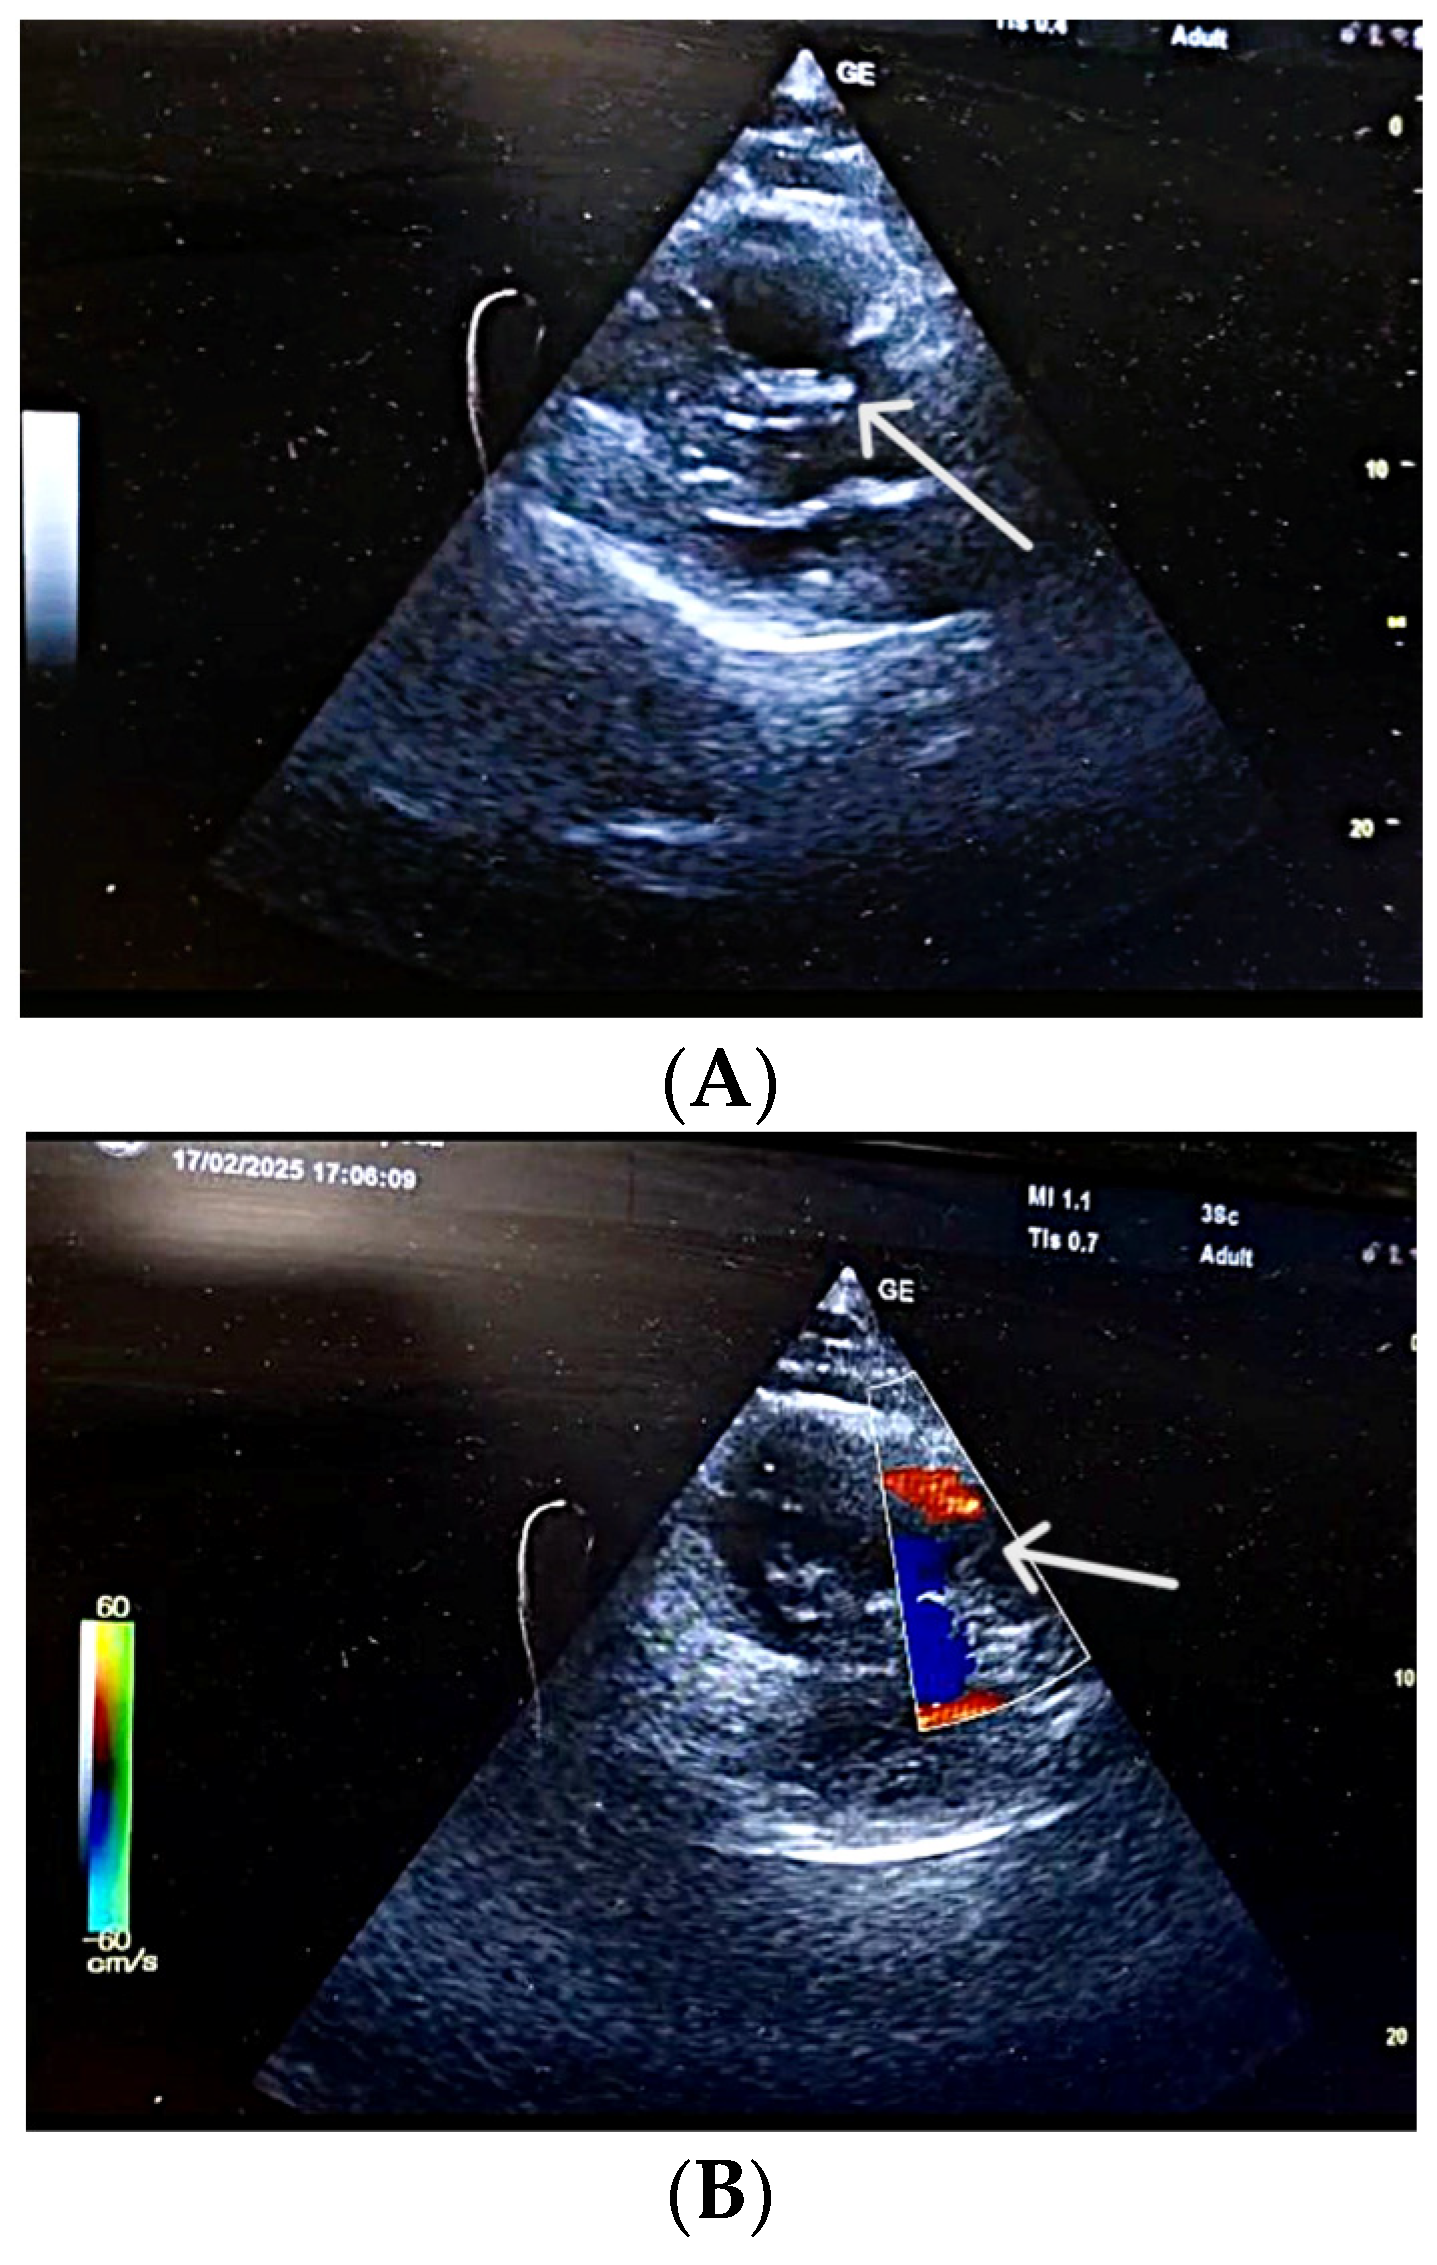

| POCUS-TTE—Parameters, Values and Risk Classification | |||

| RV/LV ratio | 1.39 | high | Intermediate-high-risk |

| TAPSE (mm) | 12 | low | Intermediate-high-risk |

| RV diameter | 46 mm (below tricuspid/pulmonary annulus) | Marked RV dilation |

| LV diameter | 33 mm | Normal size |

| RV/LV ratio | >1 | Consistent with acute RV pressure overload |

| RA size | Dilated | Elevated right-sided pressures |

| Pulmonary trunk diameter | 31 mm | Mild dilation; acute pulmonary hypertension |

| Tricuspid regurgitation, Vmax | 3.2 m/s | Increased RV pressure |

| RV—RA gradient | 40 mmHg | Significant RV overload |

| TAPSE | 12 mm | Markedly reduced RV systolic function |

| IVC | 19 mm, <50% collapse | Elevated RA pressure |

| Interventricular septum | Paradoxical motion | “D-shaped” LV; RV overload |

| Mobile RA thrombus | Large, serpentine, prolapsing through tricuspid | High embolic risk |